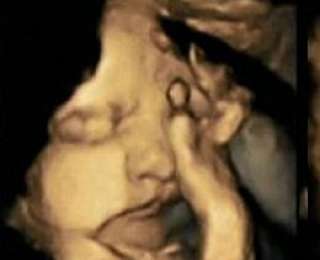

Британские ученые провели исследование, участие в которлм приняли 20 будущих матерей. 4 женщины, в среднем выкуривали по 14 сигарет в день, что позволило ученным с помощью 4D УЗИ сравнить плоды курящих и некурящих матерей. Оказалось, что во время курения ребенок, находящийся в утробе, начинает гримасничать, нервничать и всячески противиться этому процессу. В то же время ребенок некурящей матери продолжает сохранять спокойствие.

Плод курящей матери (слева) и плод некурящей матери (справа).

Плод матери, курящей по 14 сигарет ежедневно (слева), и плод некурящей матери (справа).